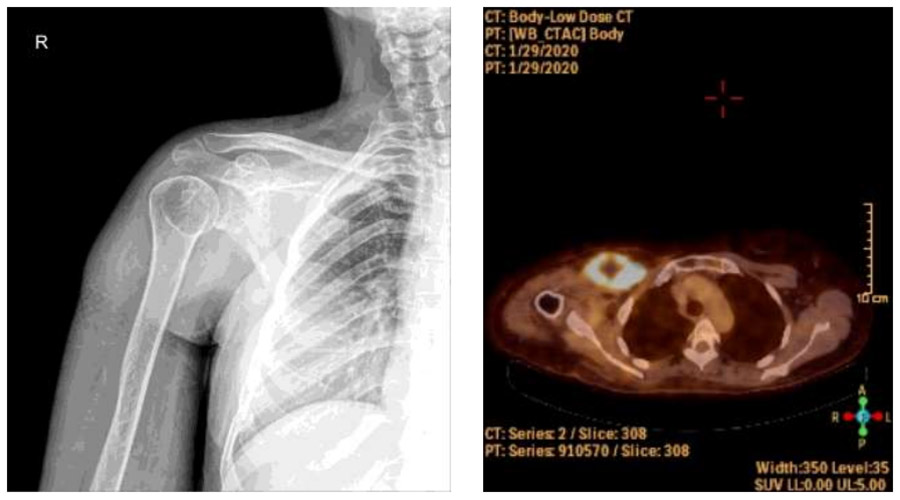

Ameliyat Öncesi: Röntgende özellik yok iken PET-CT’de artmış yoğun aktivite görülmekte